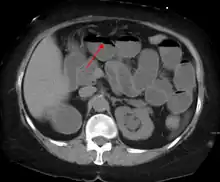

A small bowel obstruction as seen on CT

Contrast enema or small bowel series or CT scan can be used to define the level of obstruction, whether the obstruction is partial or complete, and to help define the cause of the obstruction. The appearance of water-soluble contrast in the cecum on an abdominal radiograph within 24 hours of it being given by mouth predicts resolution of an adhesive small bowel obstruction with sensitivity of 97% and specificity of 96%.[14]

Causes of bowel obstruction include adhesions, hernias, volvulus, endometriosis, inflammatory bowel disease, appendicitis, tumors, diverticulitis, ischemic bowel, tuberculosis and intussusception.[1][2] Small bowel obstructions are most often due to adhesions and hernias while large bowel obstructions are most often due to tumors and volvulus.[1][2] The diagnosis may be made on plain X-rays; however, CT scan is more accurate.[1] Ultrasound or MRI may help in the diagnosis of children or pregnant women.[1]